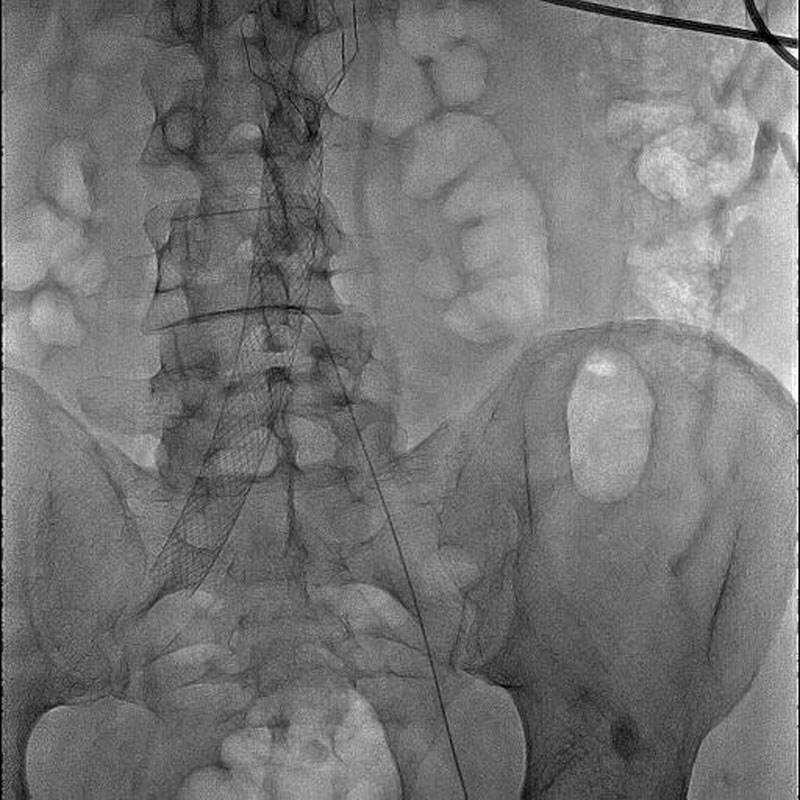

Впервые в России имплантирован венозный стент нового поколения VENOVO, выполнена реканализация и стентирование глубоких подвздошных вен у пациента с синдромом нижней полой вены, развившегося после билатерального илио-феморального тромбоза

Пироговский Центр стал российским лидером в области эндоваскулярных методик лечения хронических заболеваний вен нижних конечностей

Первая робот-ассистированная операция аорто-бедренного шунтирования